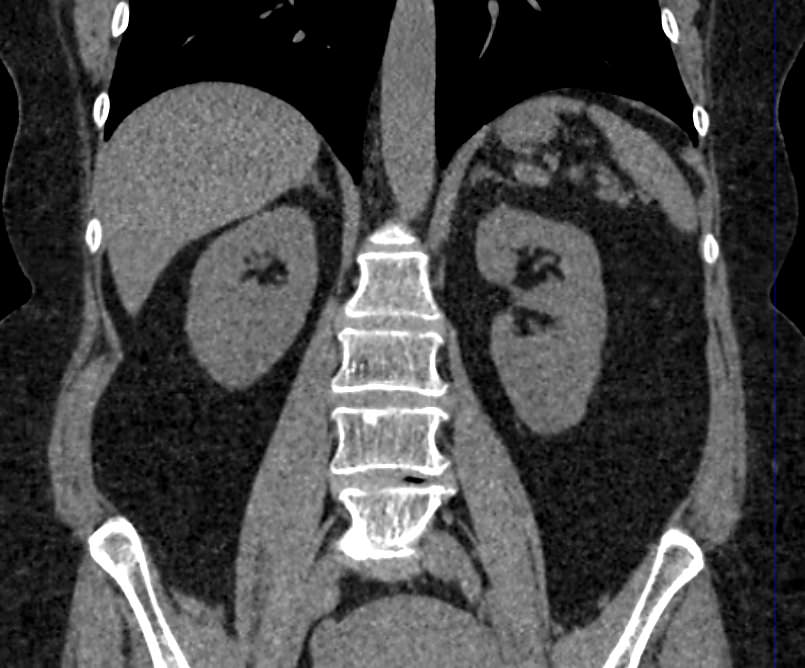

Мультиспиральная компьютерная томография (МСКТ) брюшной полости относится к современным лучевым методам исследования, с помощью которого можно оценить состояние органов брюшной полости (печени, желчного пузыря, поджелудочной железы, селезенки), прилегающих к ним кровеносных сосудов и лимфатических узлов.

С помощью мультиспиральной компьютерной томографии проводятся послойные рентгеновские снимки исследуемой области с толщиной среза от 0,5 мм. В нашей клинике исследование выполняется на компьютерном томографе экспертного класса TOSHIBA AQUILION CXL, который оснащен 128 детекторами, позволяющими получать за несколько секунд снимки брюшной полости с высокой точностью. Большое количество детекторов позволяет получить точные данные, при этом сократить время исследования и сделать минимальной лучевую нагрузку на пациента. Кроме того, инновационные технологии аппарата дают возможность сформировать объемную модель органа и окружающих структур, что также способствует проведению точной и достоверной диагностики.

При подозрении на опухоли, воспалительные процессы, гнойные очаги назначается КТ брюшной полости с внутривенным болюсным контрастированием. Для этого пациенту внутривенно вводится рентгеноконтрастное вещество на основе йода. Благодаря усиленному кровоснабжению препарат накапливается в структуре патологических образований и помогает врачу-рентгенологу выявить изменения в структуре внутренних органов.

Метод контрастирования помогает максимально точно выявить очаг патологии уже на начальной стадии, а также установить его локализацию, точные размеры, форму и особенности кровоснабжения.